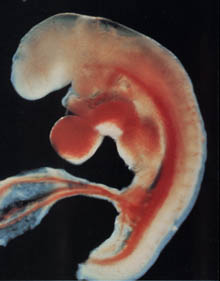

Jeśli jest czwarty tydzień położniczy, jest za wcześnie, aby mówić o płodzie. Zygota stopniowo przechodzi w stadium zarodka. Teraz nienarodzone dziecko jest prawie niewidoczną bryłą komórek, którą naukowcy nazywają morula. Pod mikroskopem będzie wyglądać jak jagoda pokryta „pryszczami”. Jeśli konsolidacja moruli w jamie macicy jeszcze nie nastąpiła, z pewnością nastąpi. I wtedy zaczyna się prawdziwa magia komórkowa.

Wielkość przyszłego płodu w 4. tygodniu położniczym jest porównywalna z „makiem”. Jego waga wynosi około 0,5 g, a wysokość 0,36–1 mm. Są to jednak dosłownie dane chwilowe. Zarodek szybko rośnie z powodu stałego podziału komórek.

Struktura zarodka

Lekarze często używają koncepcji krążka zarodkowego, który tworzy liść zarodkowy. Są to specjalne warstwy komórek:

- warstwa wewnętrzna (endoderma) spowoduje powstanie przewodu pokarmowego, wątroby i płuc, a także trzustki;

- środkowa warstwa (mezoderma) to przyszłe nerki, mięśnie, serce i naczynia krwionośne, a także szkielet dziecka;

- warstwa zewnętrzna (ektoderma) odpowiada za tworzenie układu nerwowego, głowy (w tym oczu, zębów i włosów), a także skóry.